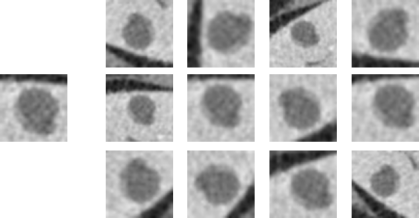

Each lesion ROI was first rotated Nrotsubscript𝑁𝑟𝑜𝑡N_{rot} times at random angles θ=[0,,180]𝜃superscript0superscript180\theta=[0^{\circ},...,180^{\circ}]. Afterwards, each rotated ROI was flipped Nflipsubscript𝑁𝑓𝑙𝑖𝑝N_{flip} times (up-down,left-right), translated Ntranssubscript𝑁𝑡𝑟𝑎𝑛𝑠N_{trans} times where we sampled random pairs of [x,y]𝑥𝑦[x,y] pixel values between (p,p)𝑝𝑝(-p,p) related to the lesion diameter (d) by p=min(4,0.1×d)𝑝𝑚𝑖𝑛40.1𝑑p=min(4,0.1\times{d}). Finally the ROI was scaled Nscalesubscript𝑁𝑠𝑐𝑎𝑙𝑒N_{scale} times from a stochastic range of scales s=[0.1×d,0.4×d]𝑠0.1𝑑0.4𝑑s=[0.1\times{d},0.4\times{d}]. The scale was implemented by changing the amount of tissue around the lesion in the ROI. As a result of the augmentation process, the total number of augmentations was N=Nrot×(1+Nflip+Ntrans+Nscale)𝑁subscript𝑁𝑟𝑜𝑡1subscript𝑁𝑓𝑙𝑖𝑝subscript𝑁𝑡𝑟𝑎𝑛𝑠subscript𝑁𝑠𝑐𝑎𝑙𝑒N=N_{rot}\times{(1+N_{flip}+N_{trans}+N_{scale})}. An example lesion and its corresponding augmentations are shown in Figure 3. All the ROIs were resized to fit a uniform size of 64×64646464\times{64} pixels using bicubic interpolation.

Refer to caption

Figure 3: Lesion ROI and augmentation examples of translation, rotation, flipping and scaling.